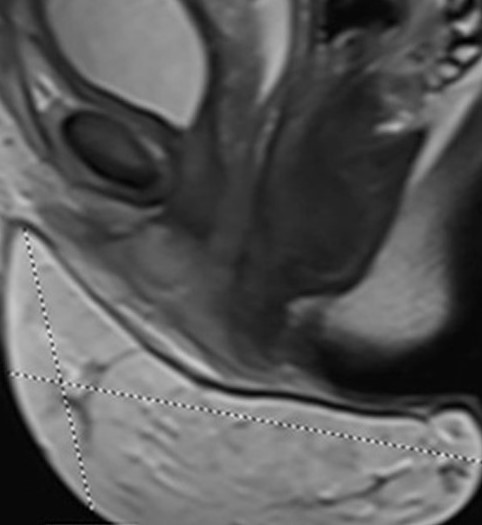

MRI οσφύος — Η βλάβη εμφανώς περιορίζεται στο δέρμα και τον υποδόριο ιστό (Ευγενική παραχώρηση Dr. V. Penopoulos)